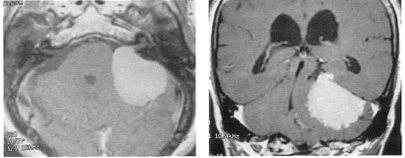

Διπλό Μηνιγγίωμα, δηλαδή ένα βαθύ περίπλοκο μηνιγγίωμα συγχρόνως με ένα απλό επιφανειακό μηνιγγίωμα και υδροκέφαλο, διαγνώσθηκαν στην ίδια ασθενή και αντιμετωπίσθηκαν πλήρως με προηγμένη, ολοκληρωμένη χειρουργική τεχνική από τον Καθηγητή Δαμιανό Σακά.

Τα μηνιγγιώματα είναι σχετικά συχνοί όγκοι που προσβάλλουν συνηθέστερα τον γυναικείο πληθυσμό. Μπορούν να ταξινομηθούν σε δύο κυρίως κατηγορίες με διαφορετικό βαθμό δυσκολίας: α) τα επιφανειακά μηνιγγιώματα που αναπτύσσονται περιφερικά, στην κυρτότητα του κρανίου, σε επαφή με την επιφάνεια του εγκεφάλου και β) τα βαθέα μηνιγγιώματα που αναπτύσσονται είτε στην βάση του κρανίου ή σε βαθεία εντόπιση κοντά στο κέντρο του εγκεφάλου.

Η χειρουργική αφαίρεση των επιφανειακών μηνιγγιωμάτων διαφέρει ανάλογα με την θέση του μηνιγγιώματος στην επιφάνεια του εγκεφάλου, απαιτεί μεγάλη επιμέλεια από την πλευρά του χειρουργού, αλλά είναι συνήθως αρκετά τυποποιημένη και ευκολότερη, ενώ η χειρουργική αφαίρεση των βαθέων μηνιγγιωμάτων διαφοροποιείται σε πολύ μεγάλο βαθμό, ανάλογα με την κάθε περίπτωση, παρουσιάζει συχνά μεγάλες δυσκολίες και απαιτεί εξελιγμένη χειρουργική τεχνογνωσία και μεγάλη εμπειρία. Η ασθενής υποβλήθηκε σε τρείς επεμβάσεις. Κατά την πρώτη, αφαιρέθηκε το επιφανειακό και ευκολότερο μηνιγγίωμα ενώ κατά την δεύτερη (δύο μήνες μετά), αφαιρέθηκε το δυσκολότερο, βαθύ, περίπλοκο μηνιγγίωμα μέσω ειδικής τεχνικής που ονομάζεται υπερπαρεγκεφαλιδική-υποσκηνιδιακή προσπέλαση, και επιτρέπει στον χειρουργό να προσεγγίσει όγκους που ευρίσκονται σε πολύ βαθεία θέση μέσα στον εγκέφαλο. Οι δύο επεμβάσεις απαιτήθηκαν διότι τα μηνιγγιώματα ευρίσκονταν σε δύο τελείως διαφορετικές θέσεις μέσα στον εγκέφαλο και η αντιμετώπιση τους μέσω μίας επέμβασης ήταν ανέφικτη. Σύντομα, μέσω μίας άλλης επέμβασης μικρής κλιμακος και διάρκειας, αντιμετωπίσθηκε ο υδροκέφαλος.

Η περίπτωση αυτή είναι πολύ ενδιαφέρουσα, διότι η ανεύρεση συγχρόνως δύο διαφορετικών μηνιγγιωμάτων, σε δύο τελείως διαφορετικές θέσεις στον εγκέφαλο, που πρέπει να αντιμετωπισθούν σε μικρό διάστημα είναι σπάνια. Η έκβαση της ασθενούς που υποβλήθηκε σε σειρά τριών επεμβάσεων, σε μικρό συνολικά χρονικό διάστημα, κρίνεται πολύ επιτυχημένη και ικανοποιητική.